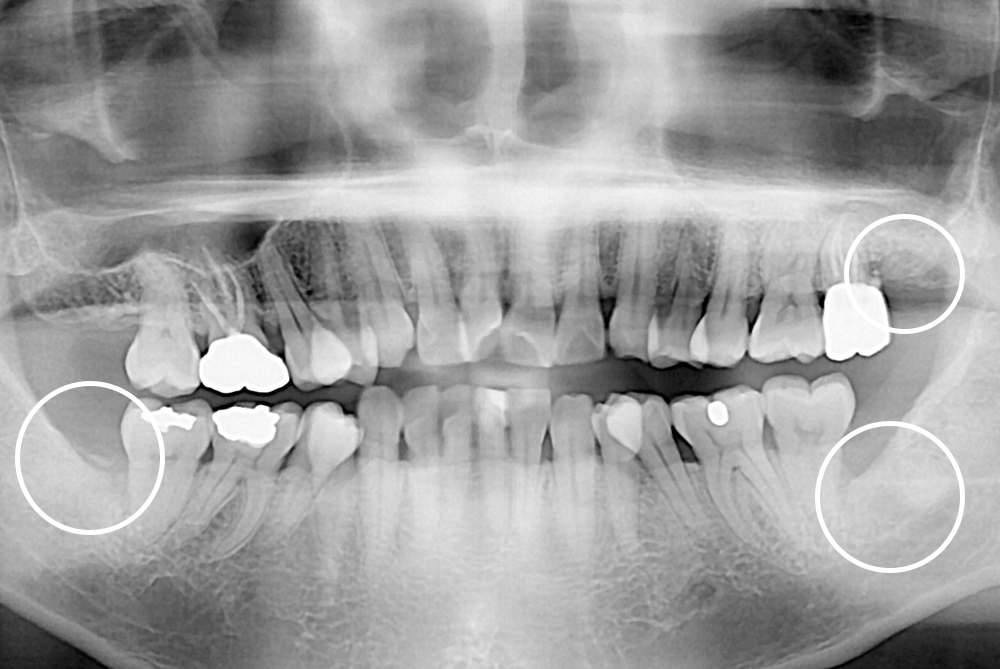

[사랑니] 매복 사랑니 발치

치료전 : 2020-03-02